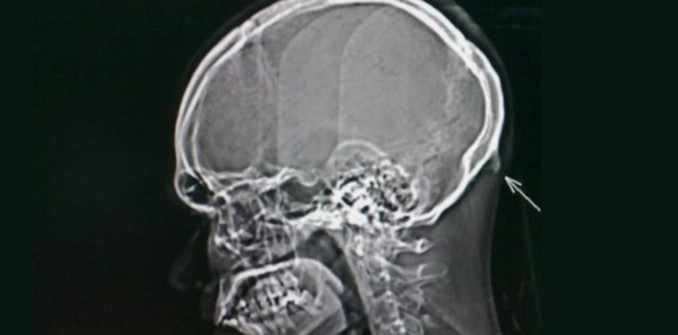

Conocido como ‘protuberancia occipital externa’, se trata de un bulto óseo que por lo general se presenta en la población joven y fue descubierto tras realizar radiografías a personas entre los 18 y 30 años donde se hallaron 218 personas con dicho fenómeno.

De las 218 personas estudiadas, el 10% tenía un hueso de alrededor de 2 cm de largo, afectando en mayor medida a los hombres, asimismo el hueso más largo hallado fue de 3.6cm en un hombre y de 2.7 cm en una mujer.

Para detectarlo basta con presionar con los dedos en la parte posterior del cráneo por encima del cuello.